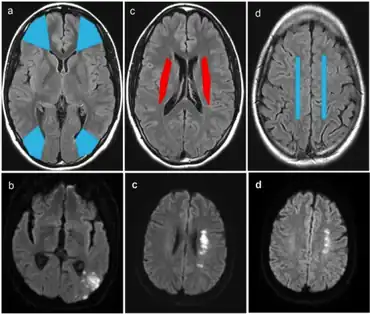

Diagnosis

Diagnosis of a cerebral vascular accident begins with a general neurological examination, used to identify specific areas of resulting injury. A CT scan of the brain is then used to identify any cerebral hemorrhaging. An MRI with special sequences called diffusion-weighted MR imaging (DWI), is very sensitive for locating areas of an ischemic based stroke, such as a watershed stroke.

Further diagnosis and evaluation of a stroke includes evaluation of the blood vessels in the neck using either Doppler ultrasound, MR-angiography or CT-angiography, or formal angiography. An echocardiogram may be performed looking for a cardiac source of emboli. Blood tests for risk factors also may be ordered, including cholesterol levels, triglyceride levels, homocysteine levels, and blood coagulation tests.

Strokes after cardiac surgery

Although the mechanism is not entirely understood, the likelihood of a watershed stroke increases after cardiac surgery. An experiment conducted in a five-year span studied the diagnosis, etiology, and outcome of these postoperative strokes. It was observed that intraoperative decrease in blood pressure may lead to these strokes and patients who have undergone aortic procedures are more likely to have bilateral watershed infarcts. Furthermore, bilateral watershed strokes are associated with poor short-term outcomes and are most reliably observed by diffusion-weighted imaging MRI. Thus future clinical research and practice should focus on the identification of bilateral stroke characteristics. This identification can help discover affected areas and increase correct diagnosis.[21]